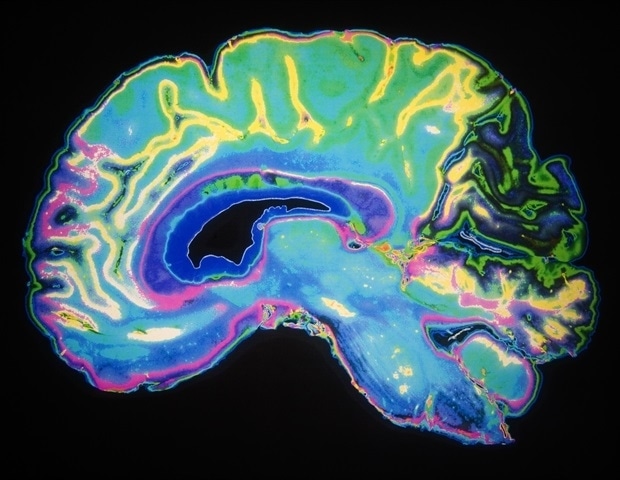

A recent study from the Massachusetts Institute of Technology (MIT) has unveiled critical insights into the brain’s functioning during periods of sleep deprivation, revealing how lapses in attention correlate with physiological changes. The research, published in the journal Nature Neuroscience, highlights that a wave of cerebrospinal fluid (CSF) flows out of the brain during these moments, a process typically associated with sleep that is essential for clearing waste products accumulated throughout the day.

During the experiments, each participant wore an electroencephalogram (EEG) cap to monitor brain activity while undergoing a modified functional magnetic resonance imaging (fMRI) scan. This advanced fMRI technique enabled researchers to observe not only blood flow but also the dynamics of CSF movement in the brain. As participants engaged in both visual and auditory attention tasks, the study noted that sleep-deprived subjects exhibited marked declines in performance.

The findings suggest a direct link between attentional lapses and CSF flow. Specifically, the researchers discovered that when attention waned, CSF was expelled from the brain, only to return during moments of cognitive recovery. “If you don’t sleep, the CSF waves start to intrude into wakefulness where normally you wouldn’t see them. However, they come with an attentional tradeoff,” Lewis explained.